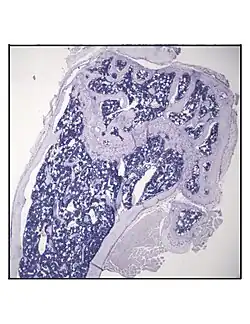

Representative distal femur histologic section of a 16-week-old C57BL/6 mouse after 6 weeks of calorie restriction demonstrating an increased quantity of marrow adipocytes.